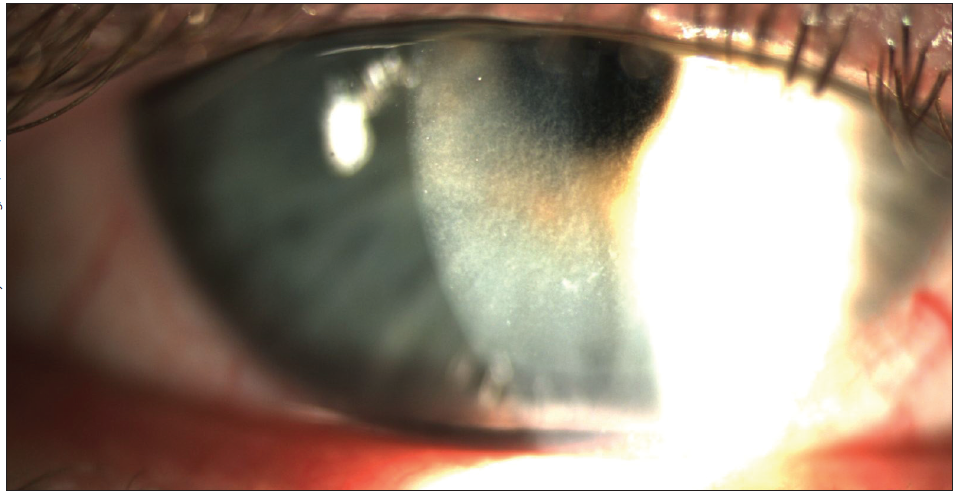

At the slit lamp, DLK is characterized by white, grainy cells underneath the LASIK flap interface (Figure 2). In its severe stages, DLK can cause corneal scarring, vision loss, and stromal melting. Patients with DLK often experience pain, foreign body sensation, photophobia, and blurry vision. Some, however, may offer no complaints, making it critical that ODs be vigilant for this complication during the early postoperative period and immediately inform the surgeon of any concerns.

Figure 2. Diffuse lamellar keratitis identified by white, grainy bands of intralamellar inflammatory cells viewed by slit lamp.

DLK is treated aggressively with steroids, one drop administered every 1 to 2 hours. I generally prescribe prednisone acetate rather than difluprednate ophthalmic emulsion 0.05% (Durezol, Alcon). Difluprednate has been associated with pressure spikes1,2 and may cause a steroid response in some patients and should therefore be used with caution. If difluprednate is prescribed, IOP should be monitored carefully. After the initiation of steroid treatment, DLK typically resolves in 5 to 8 days. If the condition persists, the surgeon may lift the LASIK flap and irrigate the interface with balanced salt solution.

Early intervention for DLK carries a better prognosis.